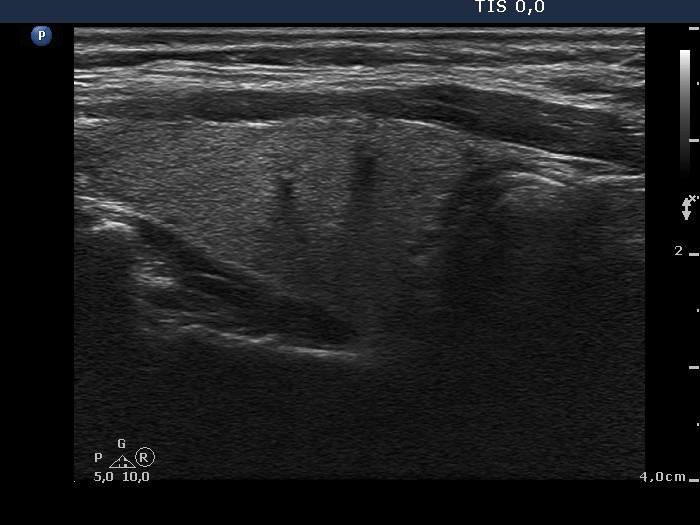

100 consecutive cases of papillary cancer - case 013 (ultrasonographic picture 2)

Right lobe, longitudinal scan. There are several small hypoechogenic areas within this previously resected lobe.